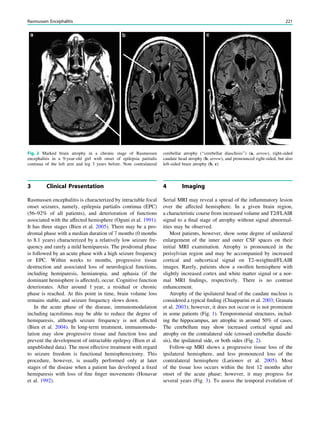

Fig. 1 Digital photogram of the brain surface before placement of a

subdural 8 9 8 grid. A second photogram was taken after grid

placement and digitally replaced by a schematic drawing detailing the

results of electrical stimulations and ictal/ intraictal EEG activity. Blue

grid contacts represent the eloquent zone, which is the motor cortex in

this case. The black area represents the epileptogenic lesion, defined

as the radiographic lesion that causes the seizures. The yellow area is

the seizure onset zone, defined as the area from which the clinical

seizures are generated. The seizure onset zone is often, but not

necessarily, congruent with the epileptogenic zone, defined as the

cortex area indispensable for the generation of seizures